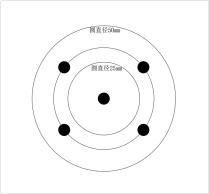

| 視場角 | 視場角靶標 |  | YY 1028-2008YY0068.1-2008 | |

| FDA認證-視場角 | 角度型視場角 |  | FDA認證 | 測量視場角 | |